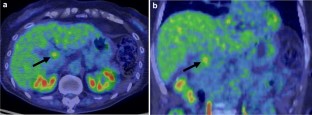

Recently, the number of reports describing patients with initially unresectable biliary tract cancer (BTC) who underwent resection in the form of conversion surgery is increasing. Gemcitabine plus cisplatin (GC) combination therapy has been reported to significantly prolong the median survival time from 8.1 to 11.7 months compared with conventional gemcitabine therapy in patients with unresectable BTC. We report the case of a patient with unresectable BTC who underwent conversion surgery with a partial response to GC combination therapy. A 78-year-old woman was diagnosed with unresectable BTC with invasion of the right hepatic artery by lymph node metastasis and liver metastases. The patient received GC combination therapy. After 6 cycles of chemotherapy, the patient achieved a partial response. The radiological findings revealed a marked shrinkage in the primary lesion and the disappearance of lymph node and liver metastases. Therefore, the patient underwent conversion surgery, including biliary tract resection and regional lymph node dissection. For postoperative follow-up, the patient was monitored without receiving adjuvant chemotherapy. The patient had not exhibited recurrence during the 12-month follow-up period. We report the case of a patient with unresectable BTC who underwent conversion surgery with a partial response to GC combination therapy.